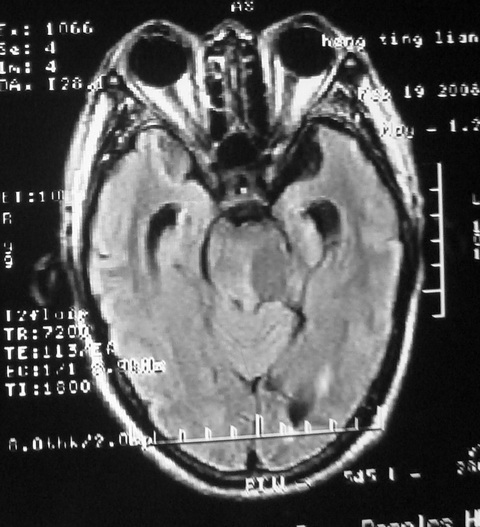

m,72,头疼,头晕两年,伴视力模糊三月,饮食呛咳两天。pe:颈部抵抗,左眼突出,左眼瞳孔约3mm,对光反射消失,双眼失明,伸舌困难,双肺呼吸音粗,心率110次/分,左上肢肌力i级,左下肢屈曲,肌张力高。现有08年2月19mri平扫及10年2月8日mri增强请会诊。ct病灶呈低密度伴散在点、片状等密度区,无明确钙化(无ct片资料可供上传)。[

脑外肿瘤,表皮样囊肿可能性大。

脑外肿瘤,囊实性,环状不规则强化,内听道扩大,考虑神经源性肿瘤

考虑表皮样囊肿。

左侧桥小脑区占位伴梗阻性脑积水----考虑 1神经鞘瘤 2室管膜瘤。

左侧桥小脑区神经鞘瘤伴梗阻性脑积水。

听神经瘤

脑外肿瘤,病灶呈匍匐蔓延,表皮样囊肿可能性大。

脑外肿瘤,病灶呈匍匐蔓延,表皮样囊肿可能性大。支持!

左侧桥脑小脑角区肿瘤并脑积水,考虑听神经瘤,脑膜瘤?

考虑听神经瘤

左侧桥脑小脑角区肿瘤并脑积水,考虑听神经瘤,